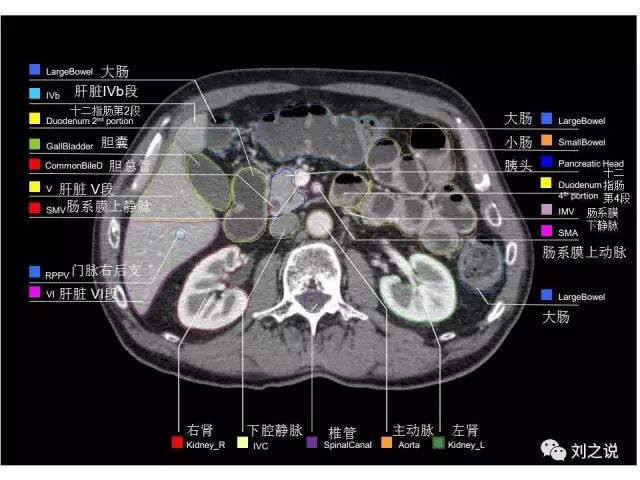

参考RTOG共识和3D-body解剖。

来源:刘之说